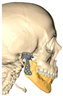

| Gender/Age (Years) | Image | MIO Preop (mm) | MIO at 6 Months (mm) | VAS Preop | VAS at 6 Months | Functional Result | Aesthetic Result | Complications |

|---|---|---|---|---|---|---|---|---|

| F/36 | ![]() | 25.9 | 36.4 | 8 | 3 | 2 | 2 | None |

| F/49 | ![]() | 15.6 | 35.4 | 9 | 4 | 2 | 2 | Partial left facial palsy |

| F/68 | ![]() | 30.5 | 40.3 | 8 | 3 | 2 | 2 | None |

| F/42 | ![]() | 26.4 | 33.5 | 7 | 2 | 2 | 2 | None |

| Average | 24.6 | 36.4 | 8 | 3 | 2 | 2 |